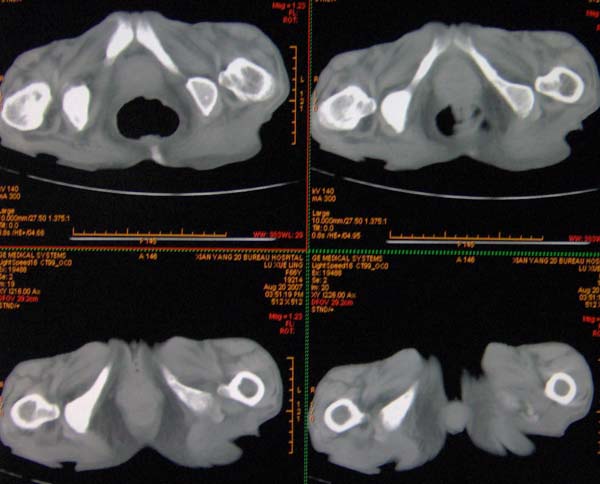

以下是引用ybing在2007-8-22 20:31:00的发言:[br]左侧髂骨溶骨样破坏;软组织肿块形成;其内未见肿瘤骨考虑纤维肉瘤或滑膜肉瘤不除外转移瘤

以下是引用qiushi在2007-8-22 21:39:00的发言:[br]双侧髂骨、骶骨侧快呈溶骨样骨质破坏,边缘模糊,左侧髂骨见骨折线,左侧髂部见软组织块影。考虑骨纤维肉瘤(中央型)伴病理性骨折,不排除骨髓瘤。建议本--周氏蛋白检查。[br] 鉴别点:[br] 骨纤维肉瘤,中央型者示边缘模糊的囊状溶骨破坏,一般无骨膜反映,可膨胀变形,突破骨皮质可形成软组织肿块,或并发病理性骨折。[br] 骨髓瘤,常表现为广泛的骨质疏松,皮质变薄或破坏,呈粟栗状、穿凿状、鼠咬状骨质破坏,边缘清晰,周围无硬化。[br] 骨转移瘤(溶骨型),表现为虫噬样、泡沫状圆形或卵圆形破坏区,很少出现软组织块影。[br][br][本贴已被 qiushi 于 2007-8-23 6:20:19 修改过]